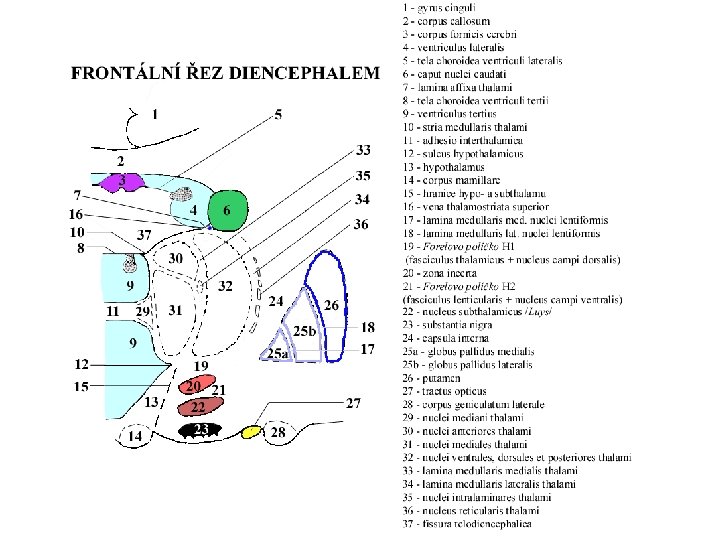

Subthalamus • uložen pod talamem - oddělen od něj Forelovým políčkem H 1 • zevně od hypotalamu - bez patrné hranice • zona incerta • nucleus subthalamicus (= corpus Luysi) • Forelova pole = campi perizonales = H pole (Haubenfelder)

Subthalamus • zona incerta – stavbou připomíná retikulární formaci – integrace podnětů z kůry a kmene – GABA tlumí ncll. intralaminares a asociační jádra talamu (podobně jako ncll. reticulares thalami) • nucleus subthalamicus (= corpus Luysi) – zapojen do soustavy bazálních ganglií (Glu do globus pallidus) – postižení: hemibalismus (hrubé nekoordinované pohyby kontralaterálních pletencových svalů) po CMP, neketonové hyperglykémii • Forelova pole = campi perizonales = H pole (Haubenfelder) – H = ansa lenticularis • H 1 • H 2 = fasciculus thalamicus = fasciculus lenticularis

Thalamus (thalamus dorsalis) • • • „sekretářka mozku“ vše kromě čichu pulvinar (dorzálně) tuberculum anterius (ventrálně) lamina medullaris medialis + lateralis thalami adhesio interthalamica (80 %) – bez významu jádra se rozdělují se podle polohy nebo zapojení – nuclei anteriores, dorsales, intralaminares, mediani, mediales, posteriores, ventrales, reticularis – specifická senzorická jádra – specifická nesenzorická jádra – nespecifická jádra – asociační jádra

Třídění thalamických jader dle polohy nuclei anteriores, dorsales, intralaminares, mediani, mediales, posteriores, ventrales, reticularis